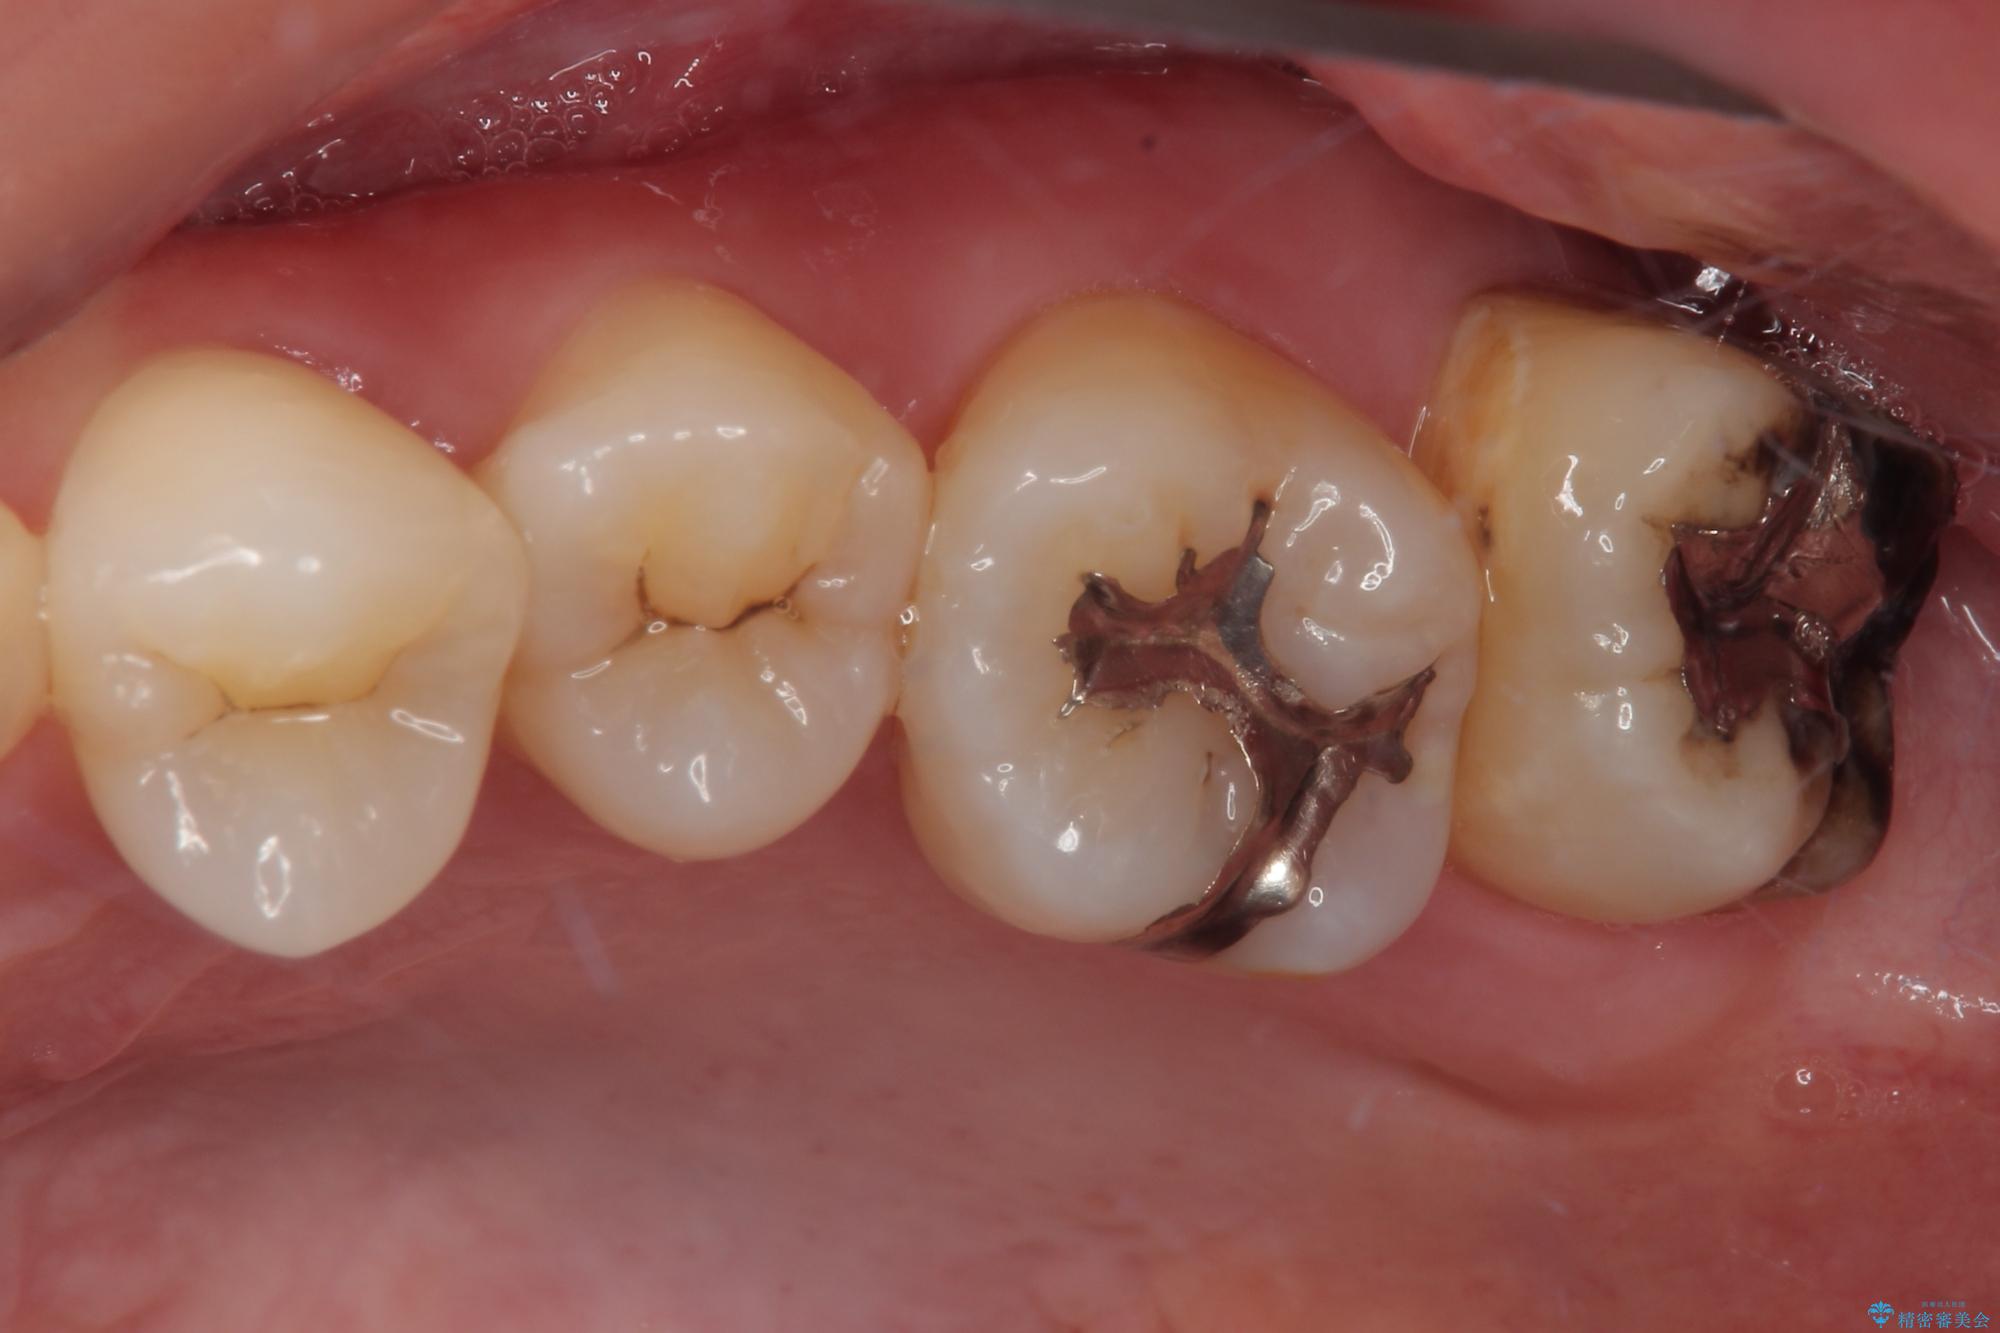

- 元々むし歯があったものの、処置が困難とのことでしたが、矯正治療を終えたので処置をしたいとのことで来院された患者様です。

左右ともに最後臼歯が頬側に顕著に突出しており、むし歯になってしまったことが想像されました。

矯正治療により処置が可能な位置に歯が移動したため、オールセラミッククラウンにて補綴治療を行うこととしました。

歯列が移動したとはいえ、左右ともに後方傾斜しており、むし歯の除去、形成(形を整える)、型取りの全てが非常に困難な処置となりました。